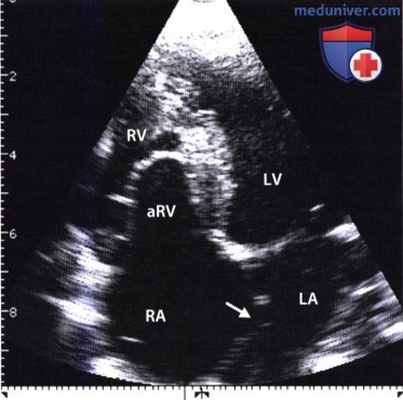

Тяжелая форма аномалии Эбштейна, выявленная при двумерной ЭхоКГ из апикальной четырехкамерной позиции.

Отчетливо видно смещение к верхушке сердца линии смыкания створок трехстворчатого клапана, связанное с протяженным сращением септальной створки с межжелудочковой перегородкой.

Значительная часть правого желудочка «атриализована» (aRV). На видеозаписи ниже представлена ЭхоКГ больного с легкой клинической формой аномалии Эбштейна.

Правый желудочек (RV) сильно увеличен и оттесняет левый (LV). В области задней стенки правого предсердия видно устье верхней полой вены.